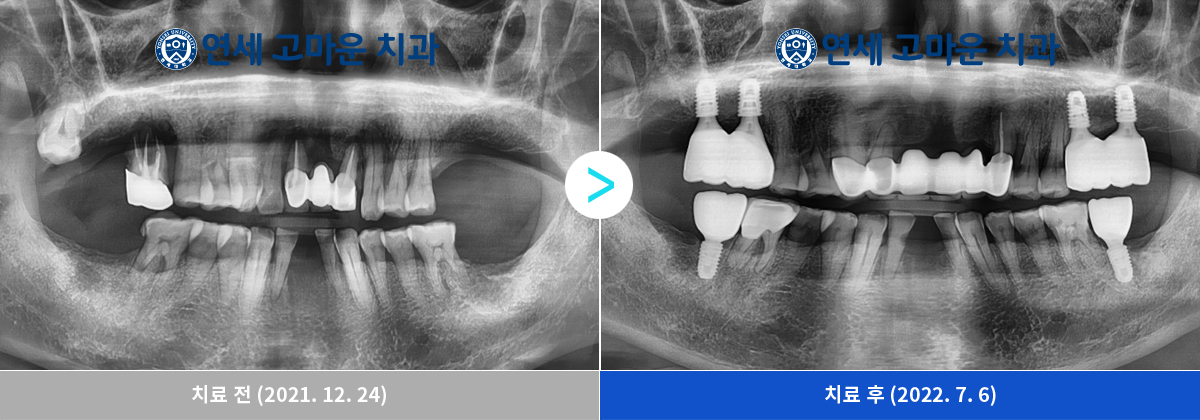

앞니 브릿지와 어금니 임플란트 6개 복합 치료 사례(281436)

치주질환이 심한 상악 앞니는 발치 후 브릿지 보철로 치료를 했으며 상실된 어금니의 경우 임플란트 6개를 식립하여 수복치료를 하였습니다.